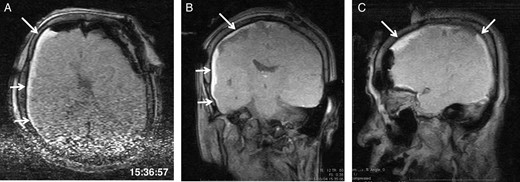

General anaesthesia was induced. Following left frontal craniotomy and dural incision, the first iMRI was performed (Fig. 1 ). One hundred fifty-eight minutes from induction, the patient regained consciousness after all anaesthetics were ceased. Tumour resection was performed with free conversation. However, after 143 min of surgery under the awake condition, the patient came to complain of excessive sleepiness though she could respond to verbal commands. Electrocorticogram (ECoG) did not detect after-discharge. The tumour was successfully removed en bloc fashion. Progressive brain swelling was not observed. The second iMRI was commenced 182 min into the awake phase (Fig. 2). Thirteen minutes from the beginning of the second iMRI scanning, the patient did not respond to noxious stimuli. When the patient was removed from the gantry, she was unconscious and had stopped spontaneous breathing. Her pupils were isocoria and did not dilate. Neither epileptic seizure nor anaphylactic reaction occurred. The peripheral oxygen saturation was not measurable, but cardiac instability or signs of vomiting were not observed. We decided to discontinue the operation under the awake status. No electrolyte imbalance or hypoglycaemia was observed. Subsequently performed iMRI identified a thin subdural haematoma in the contralateral side (Fig. 3). The fourth iMRI confirmed that most of the haematoma was evacuated following right frontal craniotomy.

The third intraoperative magnetic resonance images after intubation, axial (A), coronal (B) and sagittal (C) T1-weighted scout images show acute right-sided subdural hematoma (arrows), contralateral to the site of the craniotomy. The time of scan is superimposed.